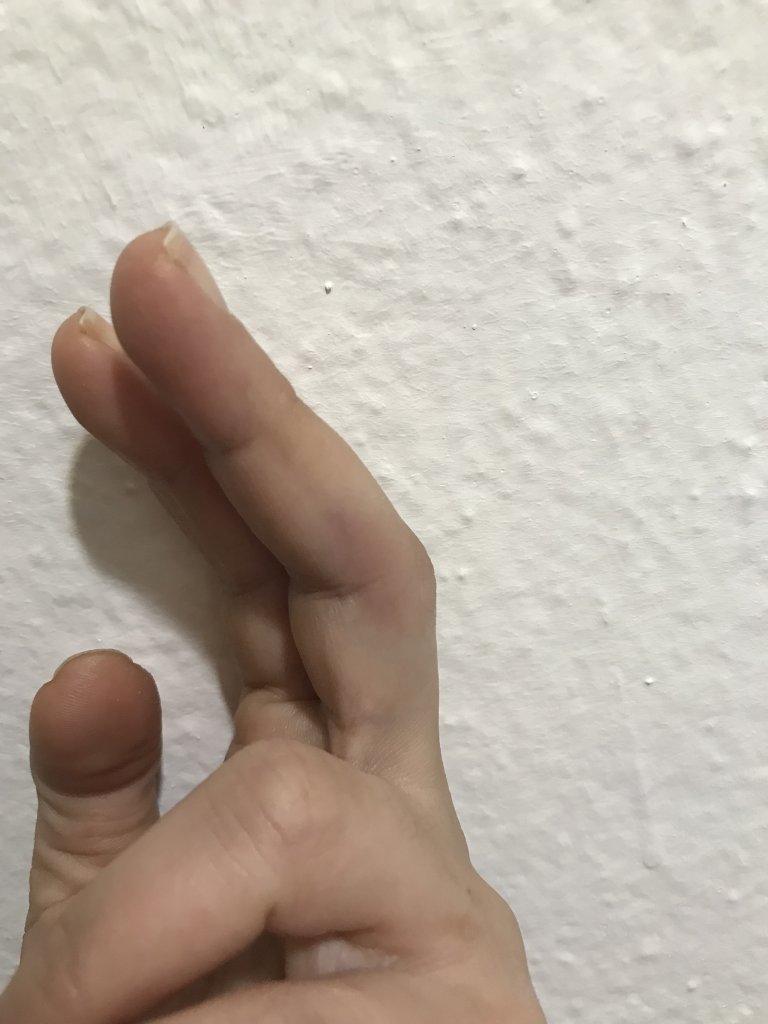

Eşim le voleybol oynarken topa nasıl vurdum bilmiyorum parmağım burkuldu mu çarptı mı döndü mü anlamadım ağrımaya başladı daha sonra kızarıklık şişme oluştu sabah acil servise gittim röntgen çekti acil Dr kırık çatlak yok dedi atel taktı ağrı kesici buz komplesi krem yazdı işe geldim ancak parmak git gide şişiyor ve hareket muhtemelen şişlikten dolayı sınırlanıyor anlamamış olabilir mi Dr sanmıyorum ama tendon diye bişey duydum ilk defa ne olduğunu da anlamadım röntgen de anlaşılmaz mıydı doku zedelenmesi daha önce yaşadım elim de çatladı ayağımda kırıldı  herşey başıma gelmiş şaka gibi böyle şişmedi hiç bu durumu yaşayan var mı aramızda yada benzer bişey aşma aşama resim ekledim ultrason anlayan vardır diye onu da koydum

herşey başıma gelmiş şaka gibi böyle şişmedi hiç bu durumu yaşayan var mı aramızda yada benzer bişey aşma aşama resim ekledim ultrason anlayan vardır diye onu da koydum